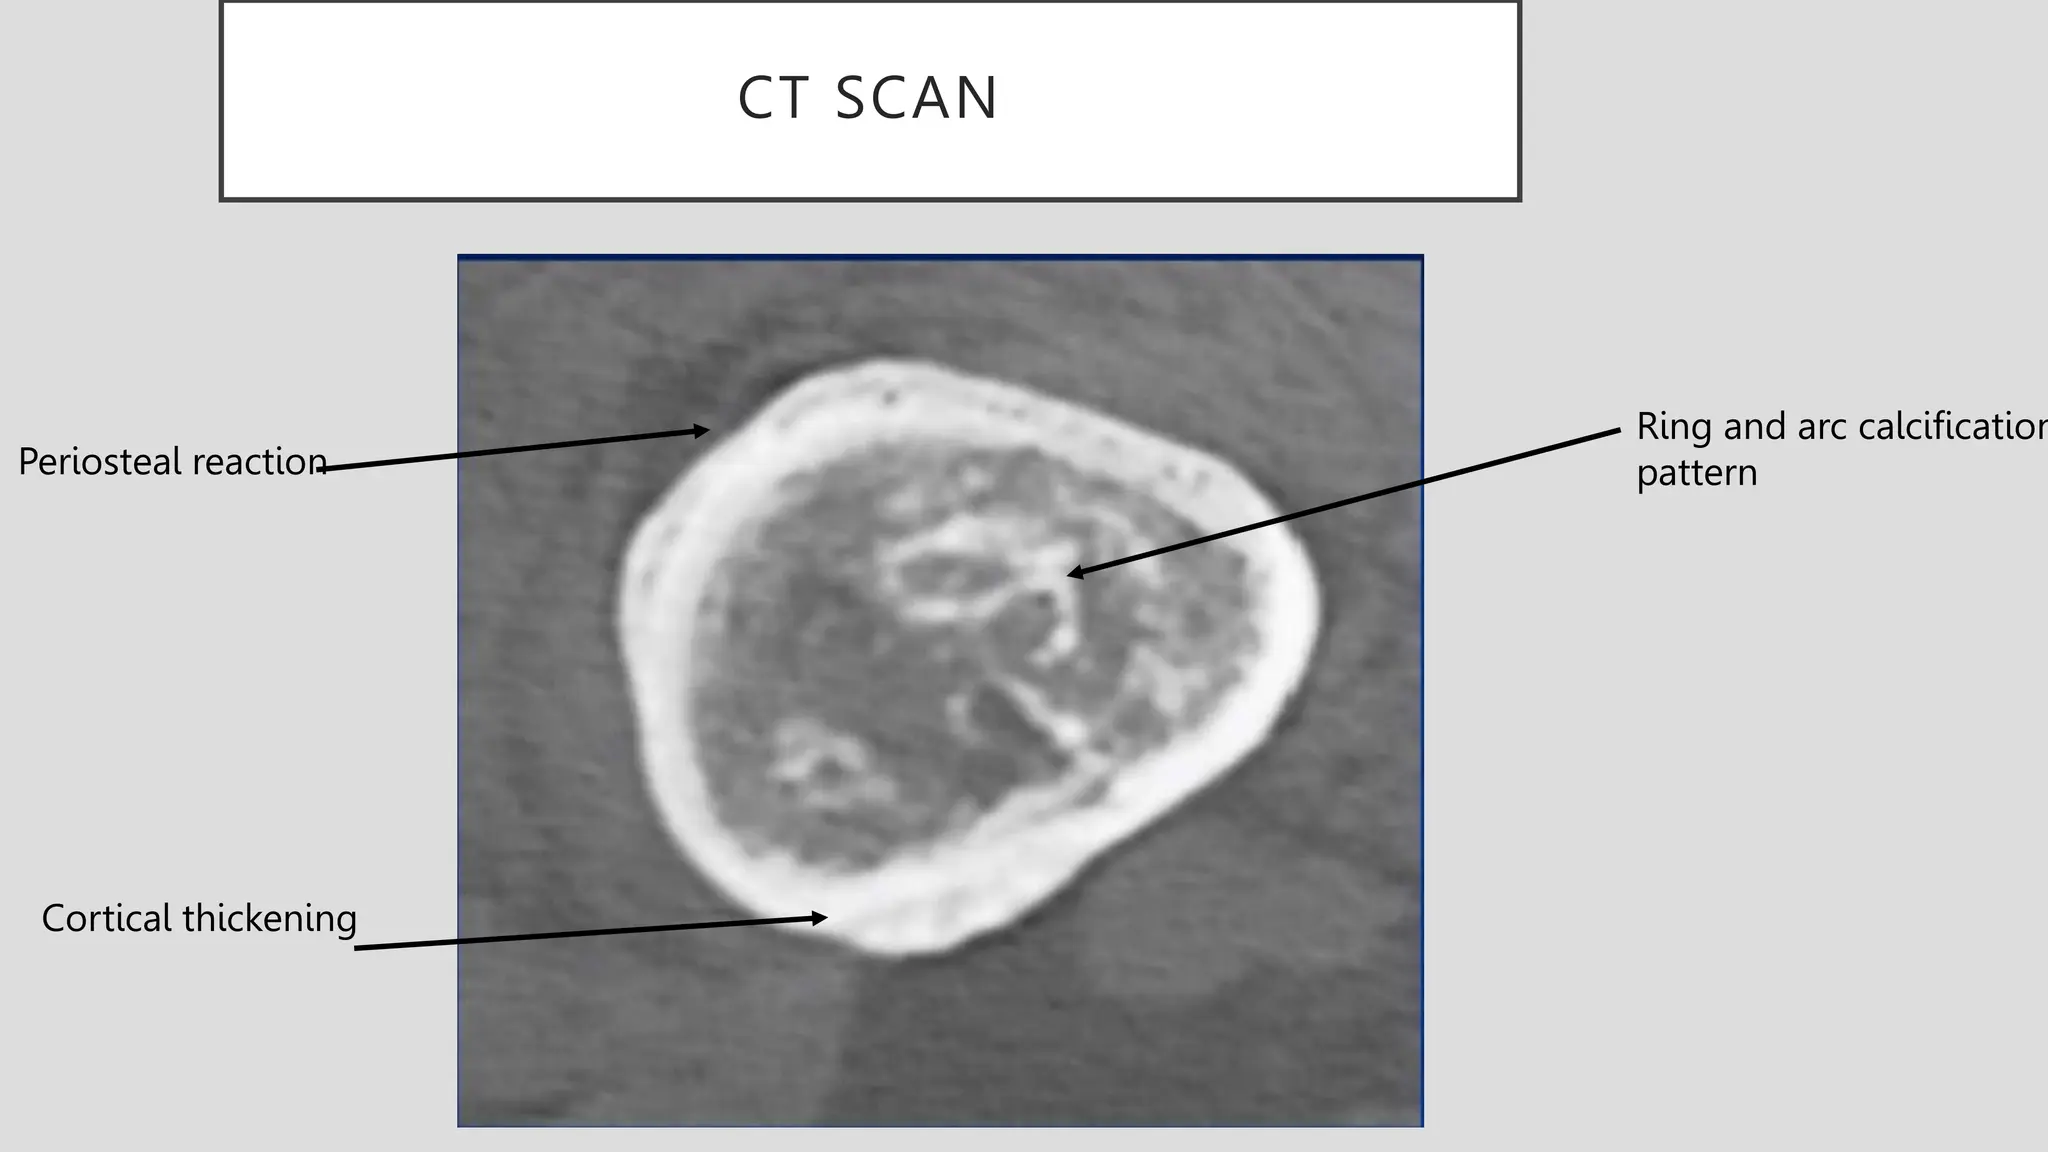

CT SCAN

Ring and arc calcification

pattern

Cortical thickening

Periosteal reaction

CT SCAN Ring andarc calcification pattern Cortical thickening Periosteal reaction